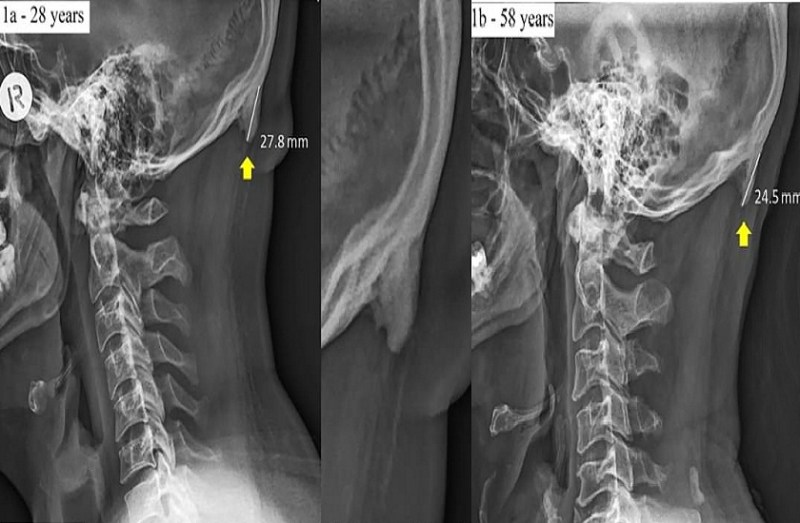

एक मीडिया रिपोर्ट के अनुसार, 18 से 30 साल के लोगों में यह बीमारी आम देखी गई है। 28 साल के युवक के सिर में 27.8 एमएम की एक हड्डी पाई गई। वहीं 58 वर्षीय के व्यक्ति में वही हड्डी 24.5 एमएम की देखी गई। यह अध्ययन 18 से 86 साल की उम्र के लोगों पर किया गया। डॉक्टर डेविड शाहर का कहना है कि इस बीमारी के पीछे की अहम वजह है लोगों का ज़रूरत से ज्यादा मोबाइल इस्तेमाल करना। डॉ.शाहर कहते हैं युवाओं का मोबाइल को इस्तेमाल करते हुए नीचे देखते रहना इस हड्डी के निकलने की प्रमुख वजह है।